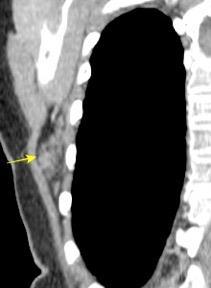

50% de los tumores de partes blandas.

Predilección varones en lipomas profundos

30% “hereditarios”

Isointenso con grasa subcutánea

Burt AM et al. Imaging review of lipomatous musculoskeletal lesions. SICOT J2017/ Murphey MD et al. From the archives of the AFIP: benign musculoskeletal lipomatous lesions. Radiographics. 2004